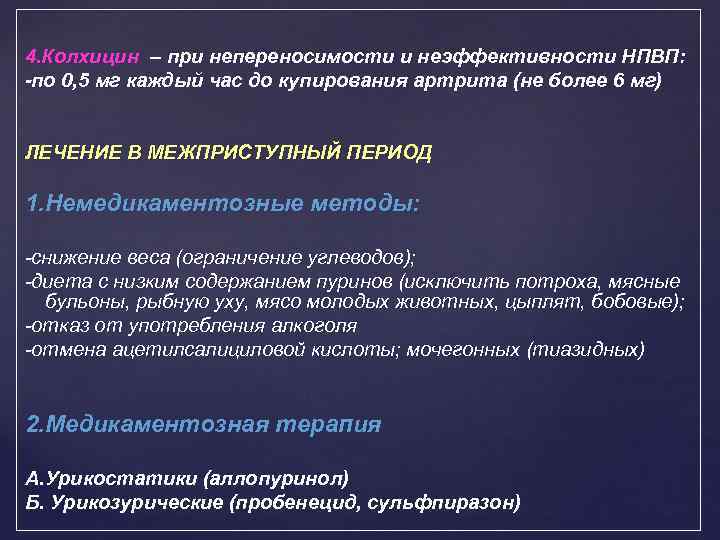

4. Колхицин – при непереносимости и неэффективности НПВП: -по 0, 5 мг каждый час до купирования артрита (не более 6 мг) ЛЕЧЕНИЕ В МЕЖПРИСТУПНЫЙ ПЕРИОД 1. Немедикаментозные методы: -снижение веса (ограничение углеводов); -диета с низким содержанием пуринов (исключить потроха, мясные бульоны, рыбную уху, мясо молодых животных, цыплят, бобовые); -отказ от употребления алкоголя -отмена ацетилсалициловой кислоты; мочегонных (тиазидных) 2. Медикаментозная терапия А. Урикостатики (аллопуринол) Б. Урикозурические (пробенецид, сульфпиразон)

4. Колхицин – при непереносимости и неэффективности НПВП: -по 0, 5 мг каждый час до купирования артрита (не более 6 мг) ЛЕЧЕНИЕ В МЕЖПРИСТУПНЫЙ ПЕРИОД 1. Немедикаментозные методы: -снижение веса (ограничение углеводов); -диета с низким содержанием пуринов (исключить потроха, мясные бульоны, рыбную уху, мясо молодых животных, цыплят, бобовые); -отказ от употребления алкоголя -отмена ацетилсалициловой кислоты; мочегонных (тиазидных) 2. Медикаментозная терапия А. Урикостатики (аллопуринол) Б. Урикозурические (пробенецид, сульфпиразон)